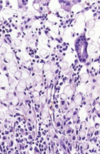

dysplasia in barretts esophagus

abrupt transition from barrett metaplasia to low grade dysplasia

note nuclear stratification and hyperchromasia

barrett

architectural irregularities, including gland within glad or “cribiform” profiles in high grade dysplasia